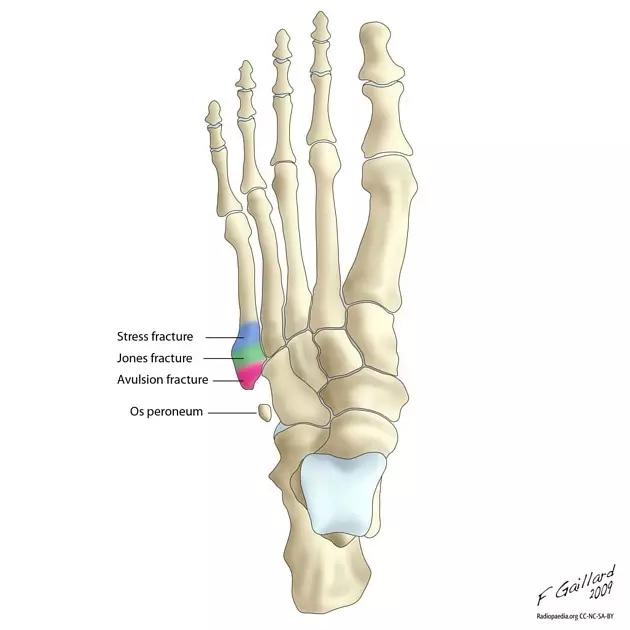

14.第五跖骨骨折

第五跖骨基底部骨折的不同类型:Stress 骨折;Jones 骨折:第五跖骨基底部以远 1 英寸内的骨折称为 Jones 骨折; Avulsion 骨折。

(来源:Radiopaedia)

Stress 骨折(来源:OrthoInfo-AAOS)

Jones 骨折正位片(来源:Radiopaedia)

Jones 骨折斜位片(来源:Radiopaedia)

第五跖骨骨折还有 dancer’s fracture。